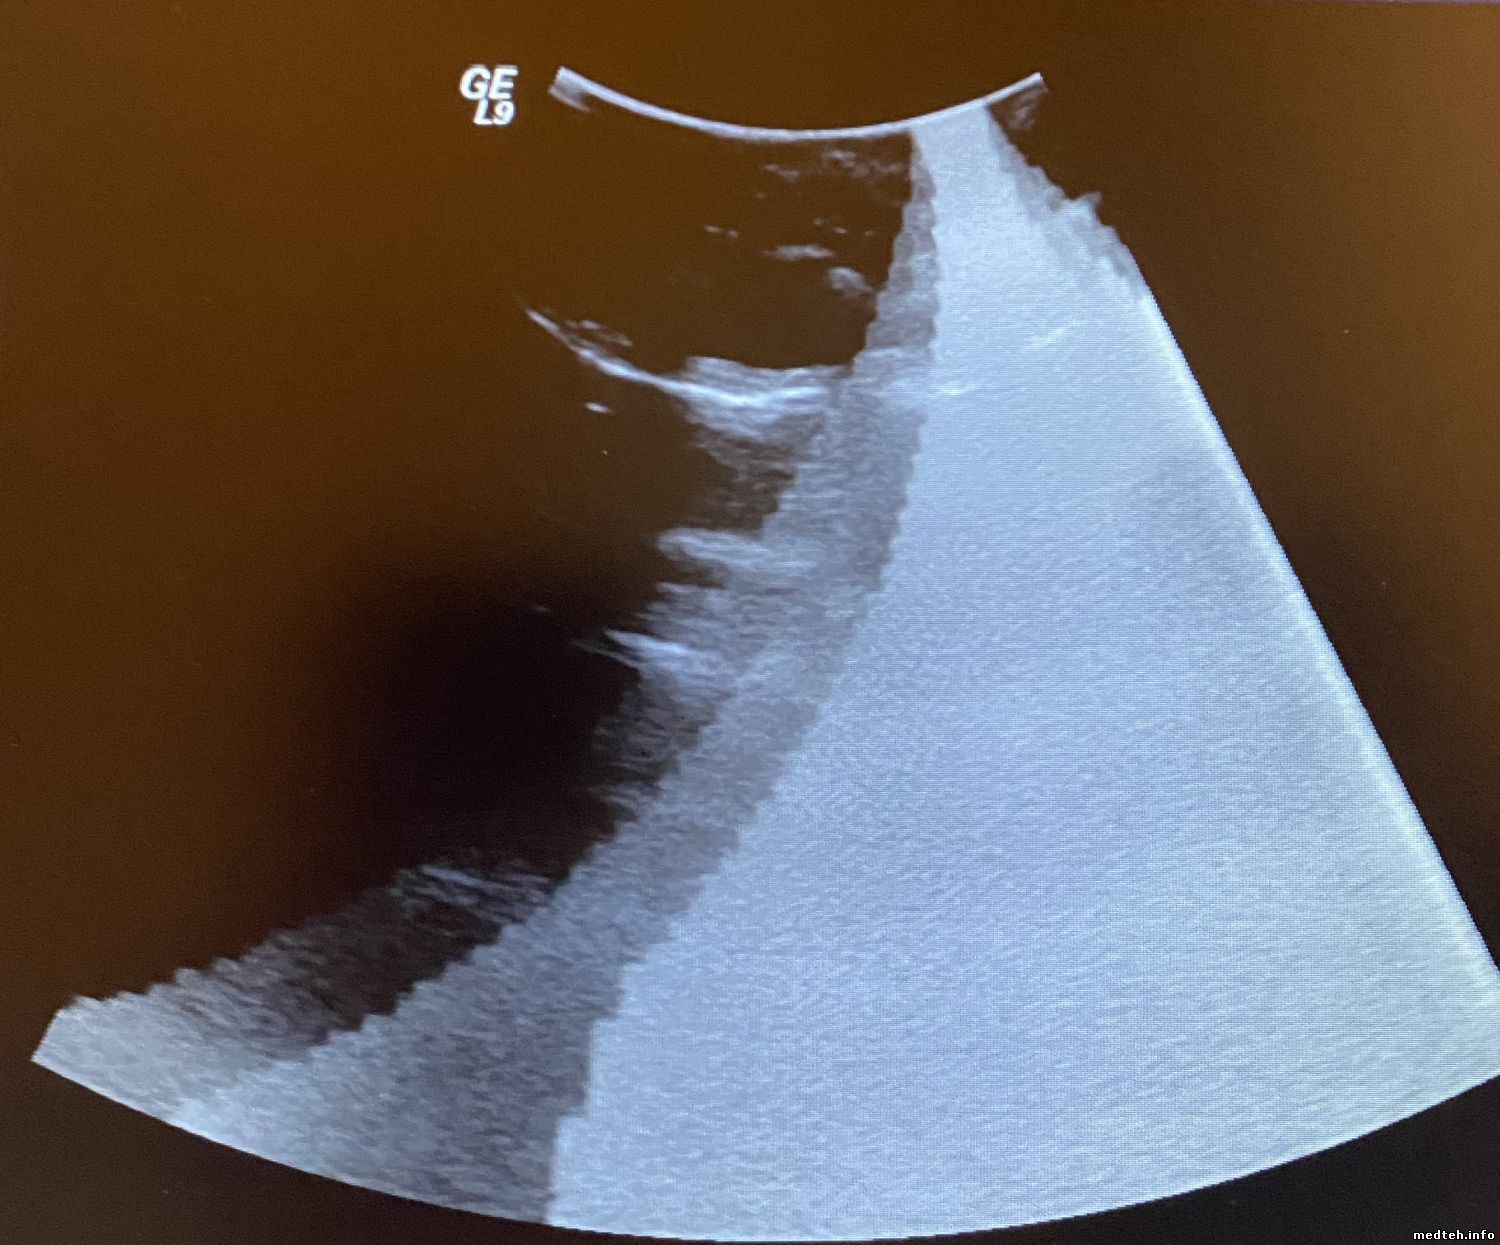

У меня по изображении Logiq 9 BT 3 появился атрефакт - на картинках. виден разной формы на всех датчиках...

боковой - круг на вагинальном, центральный конус на линейке, на конвексе ...

На линейке - http://www.medteh.info/_fr/52/3169031.jpg